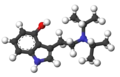

| Wzór sumaryczny |

C16H24N2O | ||||||||

4-Hydroksy-N,N-diizopropylotryptamina – psychodeliczna substancja psychoaktywna z rodziny tryptamin.

Efekty działania 4-HO-DiPT są zbliżone do LSD i psylocybiny, jednak utrzymują się tylko 2 – 3 godziny. Zgodnie z TIHKAL dawkowanie tej substancji waha się w przedziale 15 – 20 mg. Podobnie jak wszystkie pochodne DiPT, 4-HO-DIPT może wpływać na zmysł słuchu.